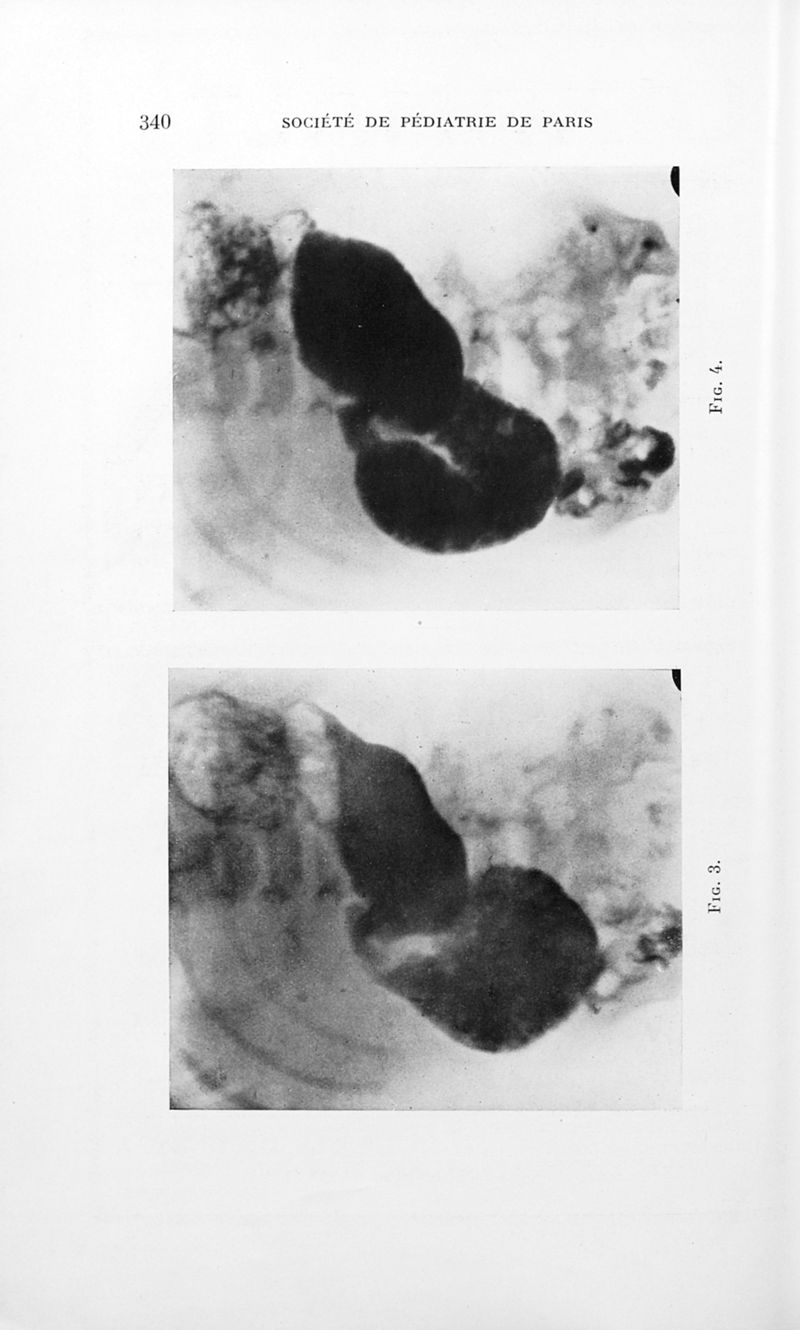

Bulletins de la société de pédiatrie de Paris

Tome trente-quatrième. - Paris : Masson et Cie, 1936.